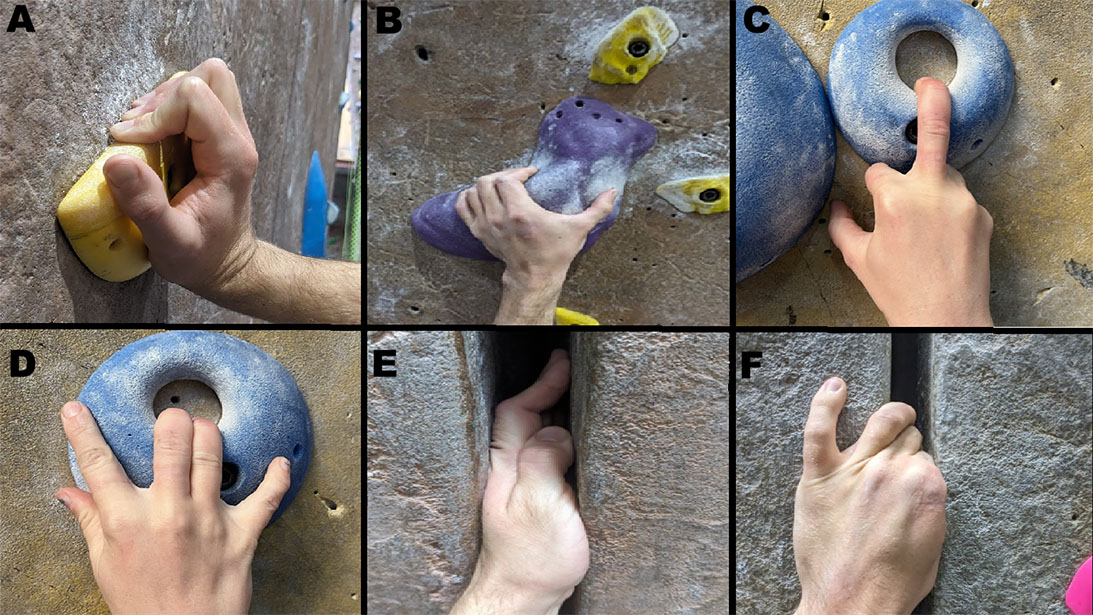

Upper extremity injuries increase as rock climbing ascends

Rock climbing is a popular sport around the word and is gaining in popularity.